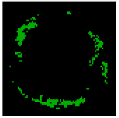

The result of the clustering algorithms will be strongly affected by the presence of outliers that do not belong to any of the clusters [28]. The purpose of outlier detection is to find small groups of pixels that are not similar to the rest of the pixels belonging to the same cluster [72]. Figure 5 illustrates the outliers with dark green, light green, etc., in an NC image. The zoomed area (b) is indicated by the blue box in the original image (a).

Figure 5.

Outliers in an NC image: (a) original image, and (b) zoomed area.

To provide more reliable results, outliers should be removed from the generated clusters. NC and DC images play an important role in TCFA detection; therefore, their outliers are removed for modifying the training set. First, the Euclidian distance between pixels belonging to the NC and its centre are calculated. Then, for each pixel in the NC image, if its distance is greater than the defined threshold value (TNC), then this pixel is an outlier, and its intensity should be replaced with zero. Based on the sub experiments, the value of TNC is changed, and intra-cluster distance (the distance between pixels and the centroid within a cluster) for the NC image are calculated. The value of TNC = 200 gave the best result for the minimum distance between pixels of the NC and its centre. In addition, outliers of DC image are removed in the similar way [45].